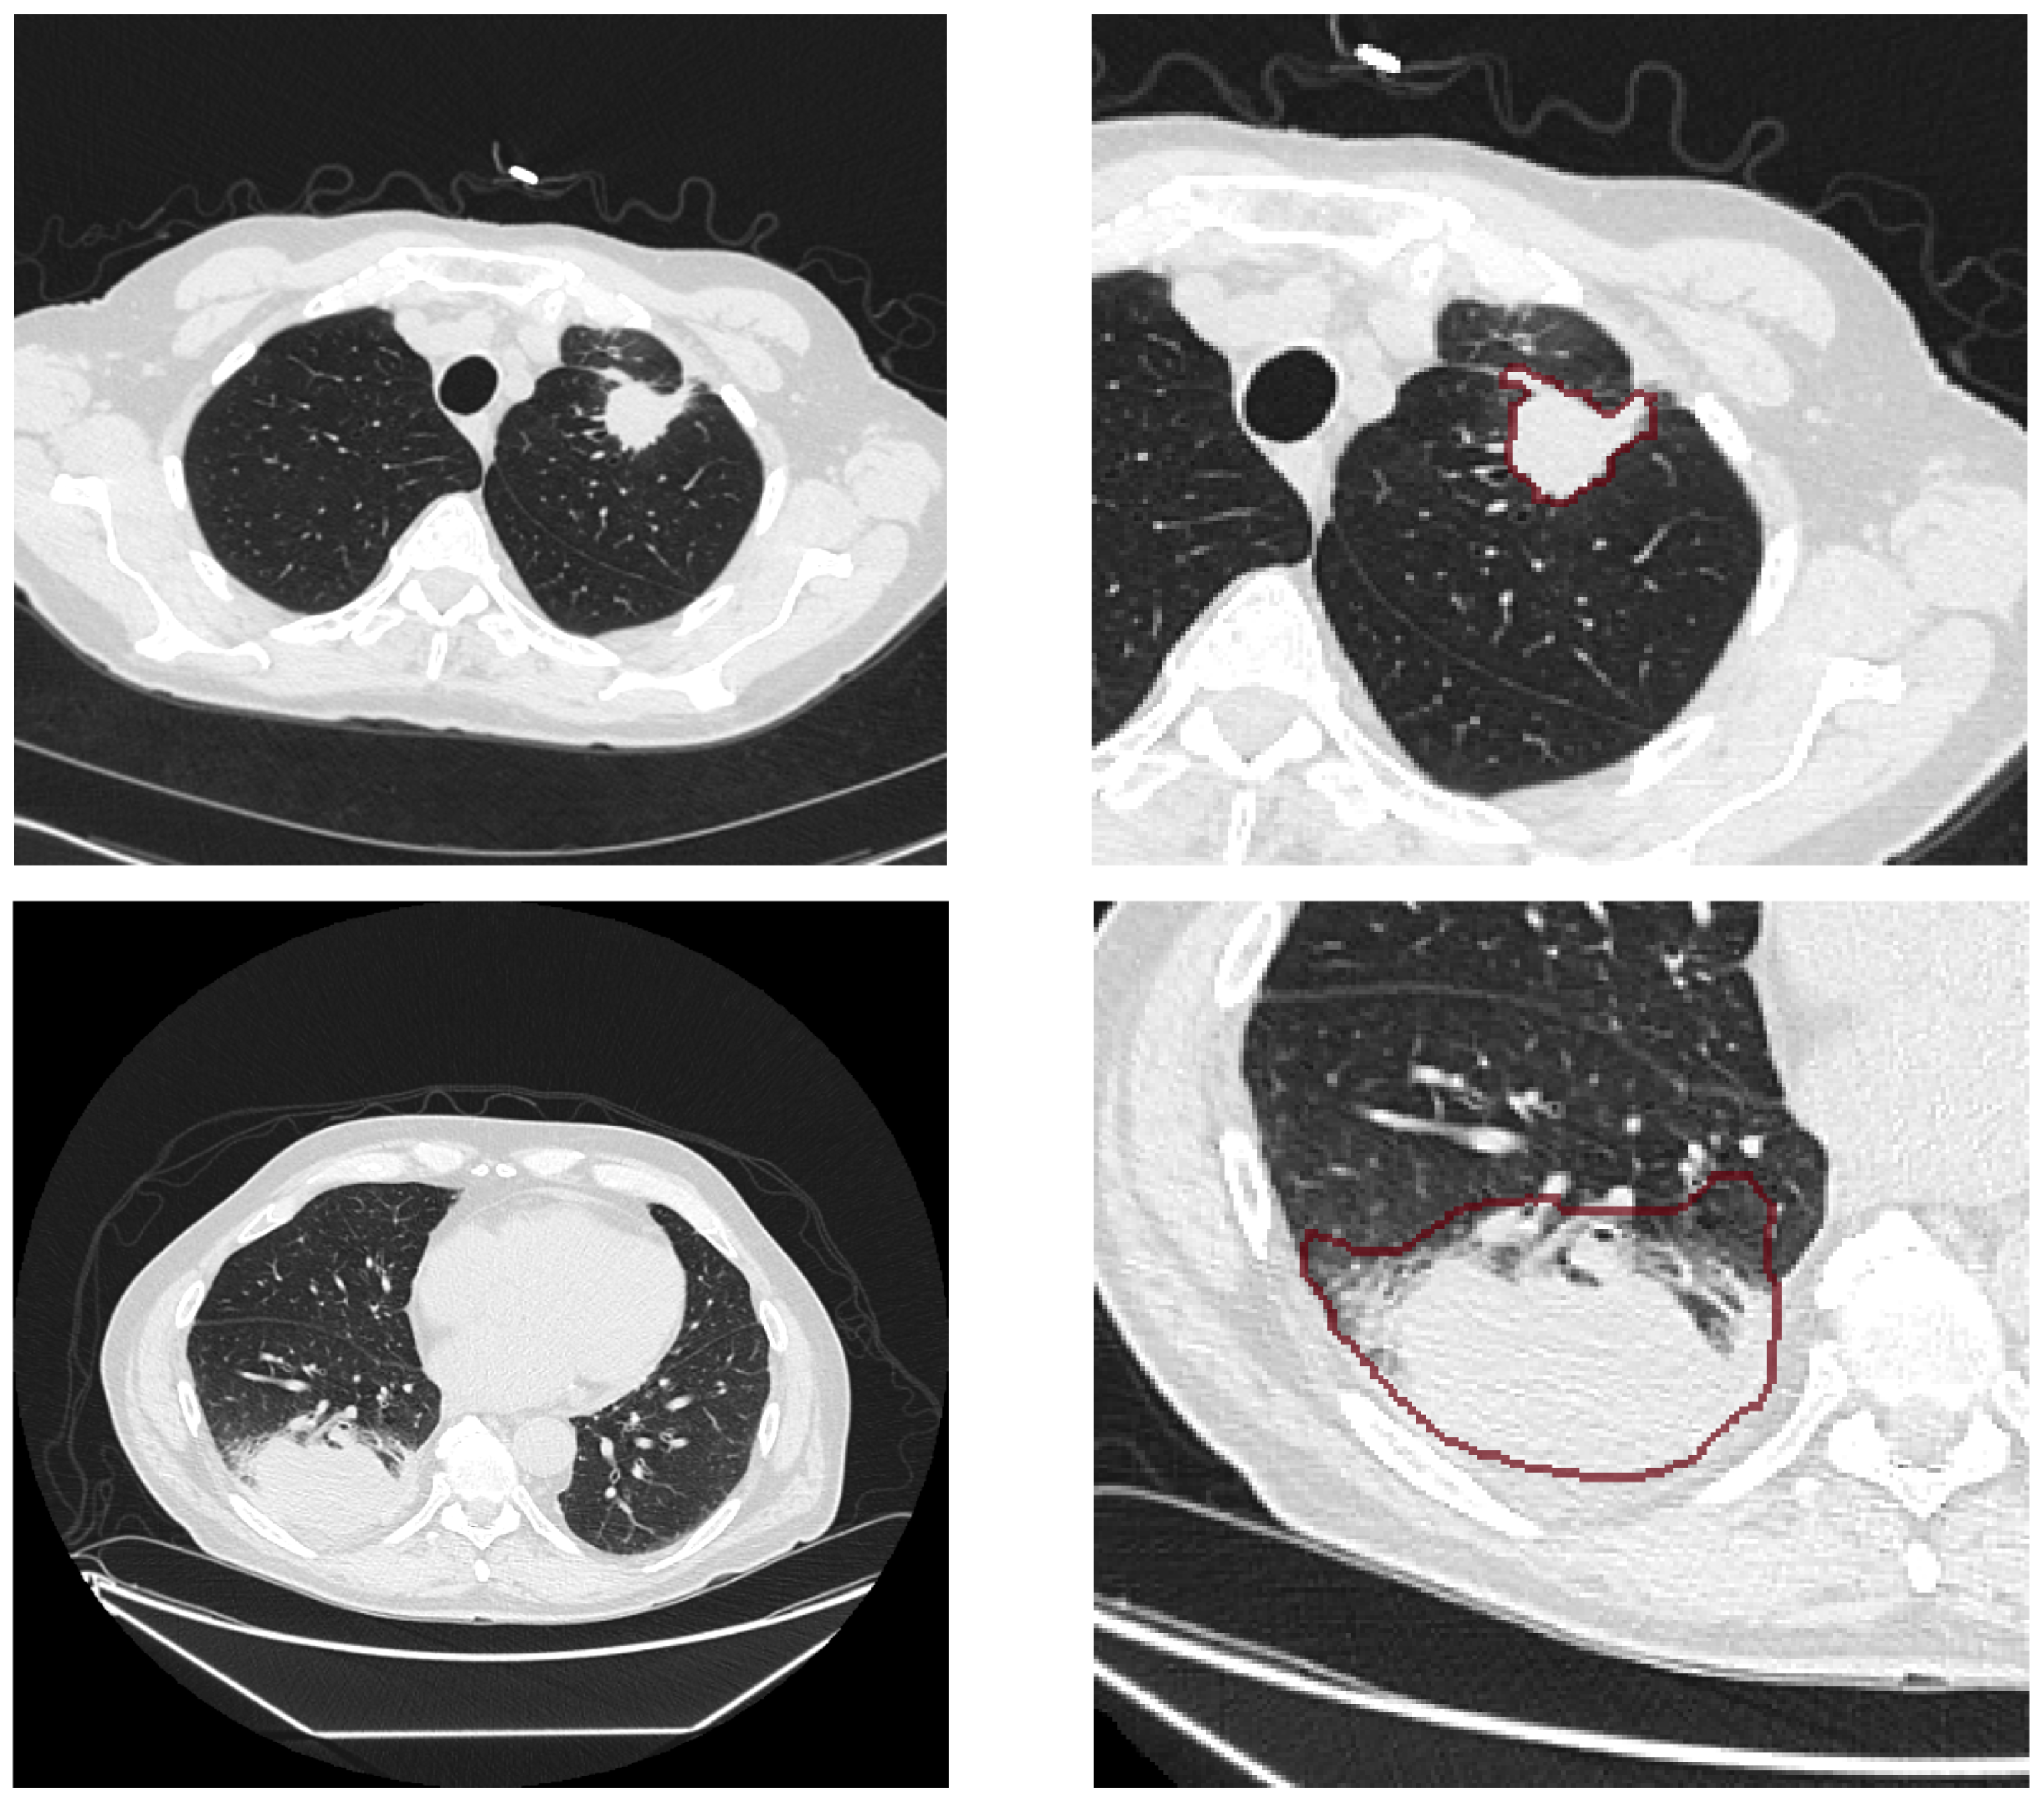

3.2. Data Preprocessing